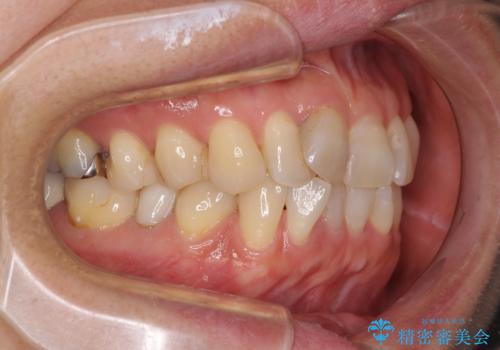

- 前歯のデコボコを気にして来院された患者様です。

舌突出癖により、上下前歯がなかなか接触せずに治療期間を要しましたが、舌のトレーニングにより無事に治療を終えることができました。

- 治療期間

- 1年10ヶ月